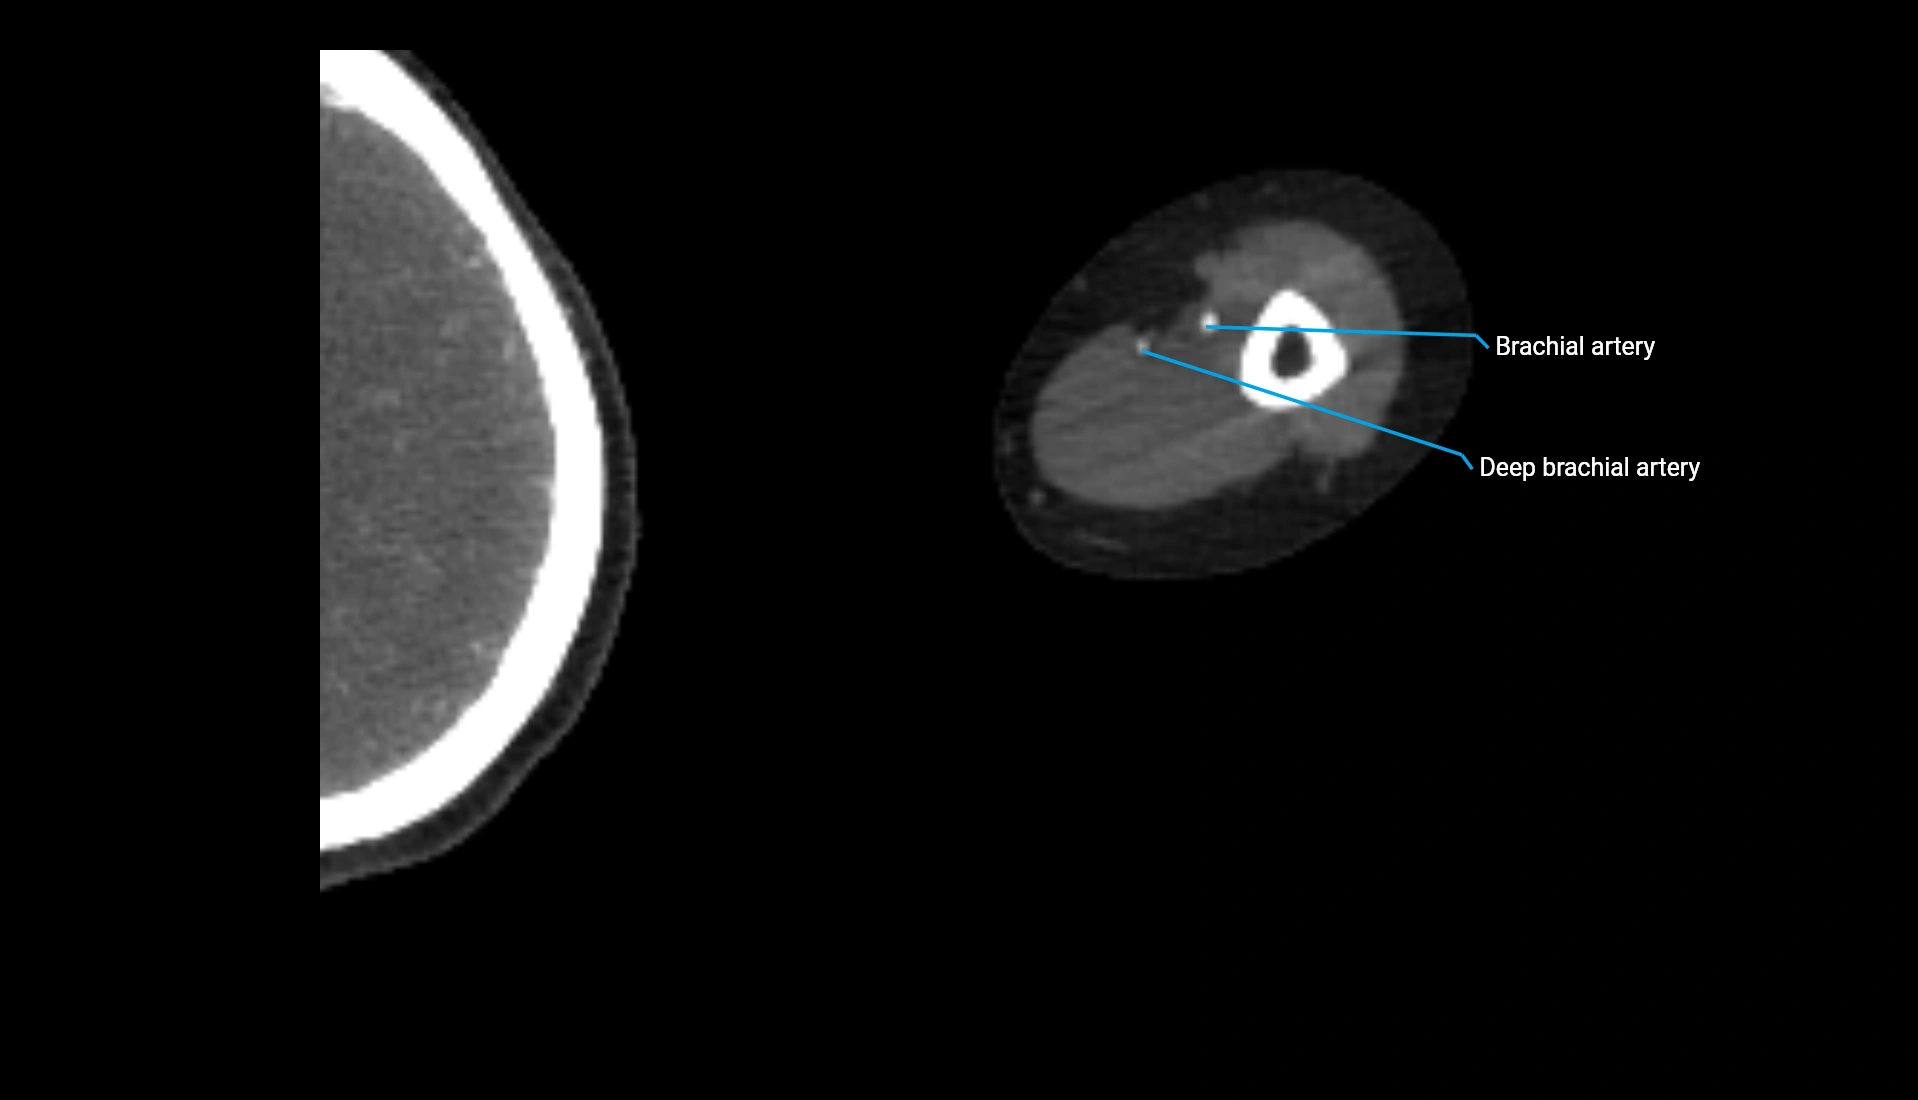

CT Appearance

Non-Contrast CT:

• Cortex: High-density, sharply defined

• Subchondral bone: Dense cancellous matrix

• Articular surface: Smooth concave contour articulating with the capitellum

• Excellent for evaluating bone integrity, alignment, and subtle fractures

Post-Contrast CT:

• Bone: No enhancement

• Joint capsule and synovium: Mild enhancement outlining the joint

• Improves contrast between soft tissues and bony margins

• Useful in detecting subtle joint abnormalities or postoperative changes